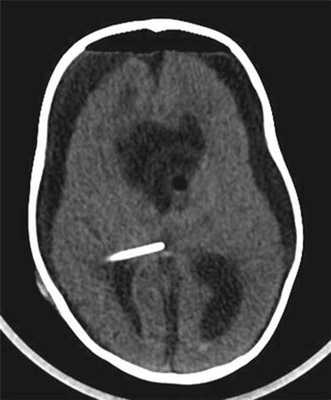

Контрольная КТ головного мозга с контрастным усилением остатков опухоли не выявила (рис. 6).

Рисунок 6. Контрольная компьютерная томография с контрастным усилением после удаления опухоли. Остатков опухоли не выявлено. Ребенок выписан в удовлетворительном состоянии на 14-е сутки после операции.